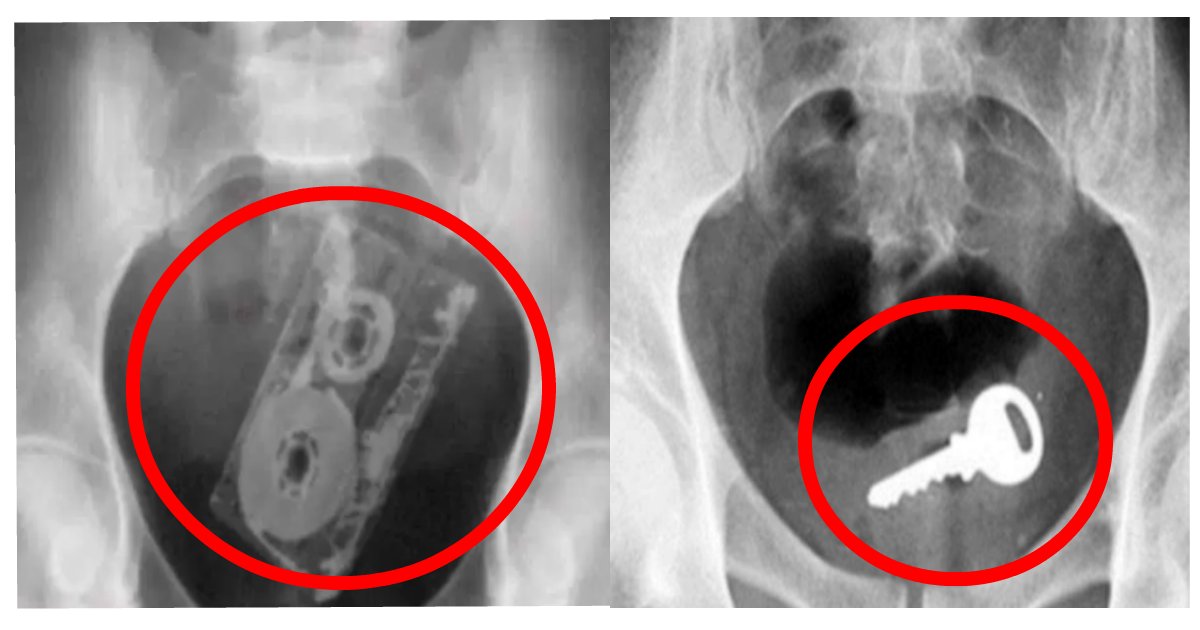

鍵

写真: dengekiranking.net/inbutt13

鍵は飲みこんでしまって病院で取ってもらう、という方は結構いらっしゃると思いますが、なぜかお尻から発見されることもよくあるんだとか。一体鍵で何を開けようとしたか謎ですが、興味本位で入れてみるものでがありませんね。

カセットテープ

写真: dengekiranking.net/inbutt13

腹部のひどい痛みを訴え、病院を受診した若い男性。興味本位でカセットを入れてしまったんだそうですが、なぜそのような考えにたどり着くのかは分かりません。このせいで、直腸が裂けてしまい、お腹を何針も縫う大手術にまで至ったようです。